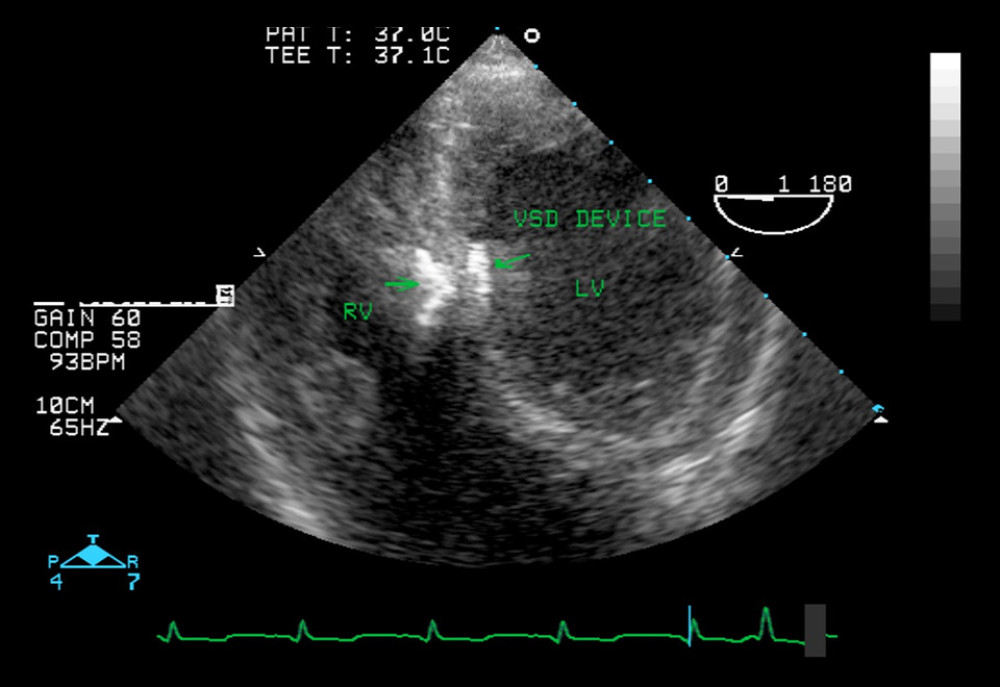

from www.youtube.com

Left to right shunt (ventricular septal defect) YouTube